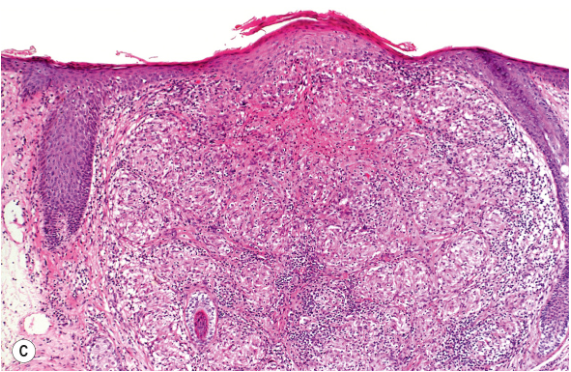

Q

What do you see here

A

Papulopustular subtype rosacea

dense dermal infiltrate of lymphocytes, predominantly surrounding hair follicle